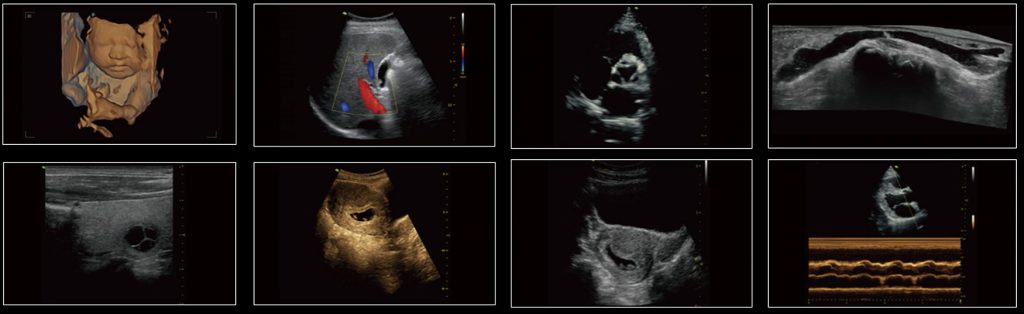

- Pulse Wave Doppler & HPRF

- Color/Power/Directional Power Doppler Flow Imaging

- Phase-inversion/ Tissue Harmonic Imaging

- Vfusion (Spatial Compound Imaging)

- VSpeckle (Speckle Reduction Imaging)

- Tview (Trapezoid Imaging)

- Triplex 2D/Color/PW

- Auto trace in PW/CW

- B+CF simultaneously

- Cardiac calculations

- OB calculations and tables

- Gynecological calculations

- Smart 3D

- 4D module

- Auto OB measurement package (BPD, OFD,HC, AC, FL)

- Auto Bladder Volume measurement